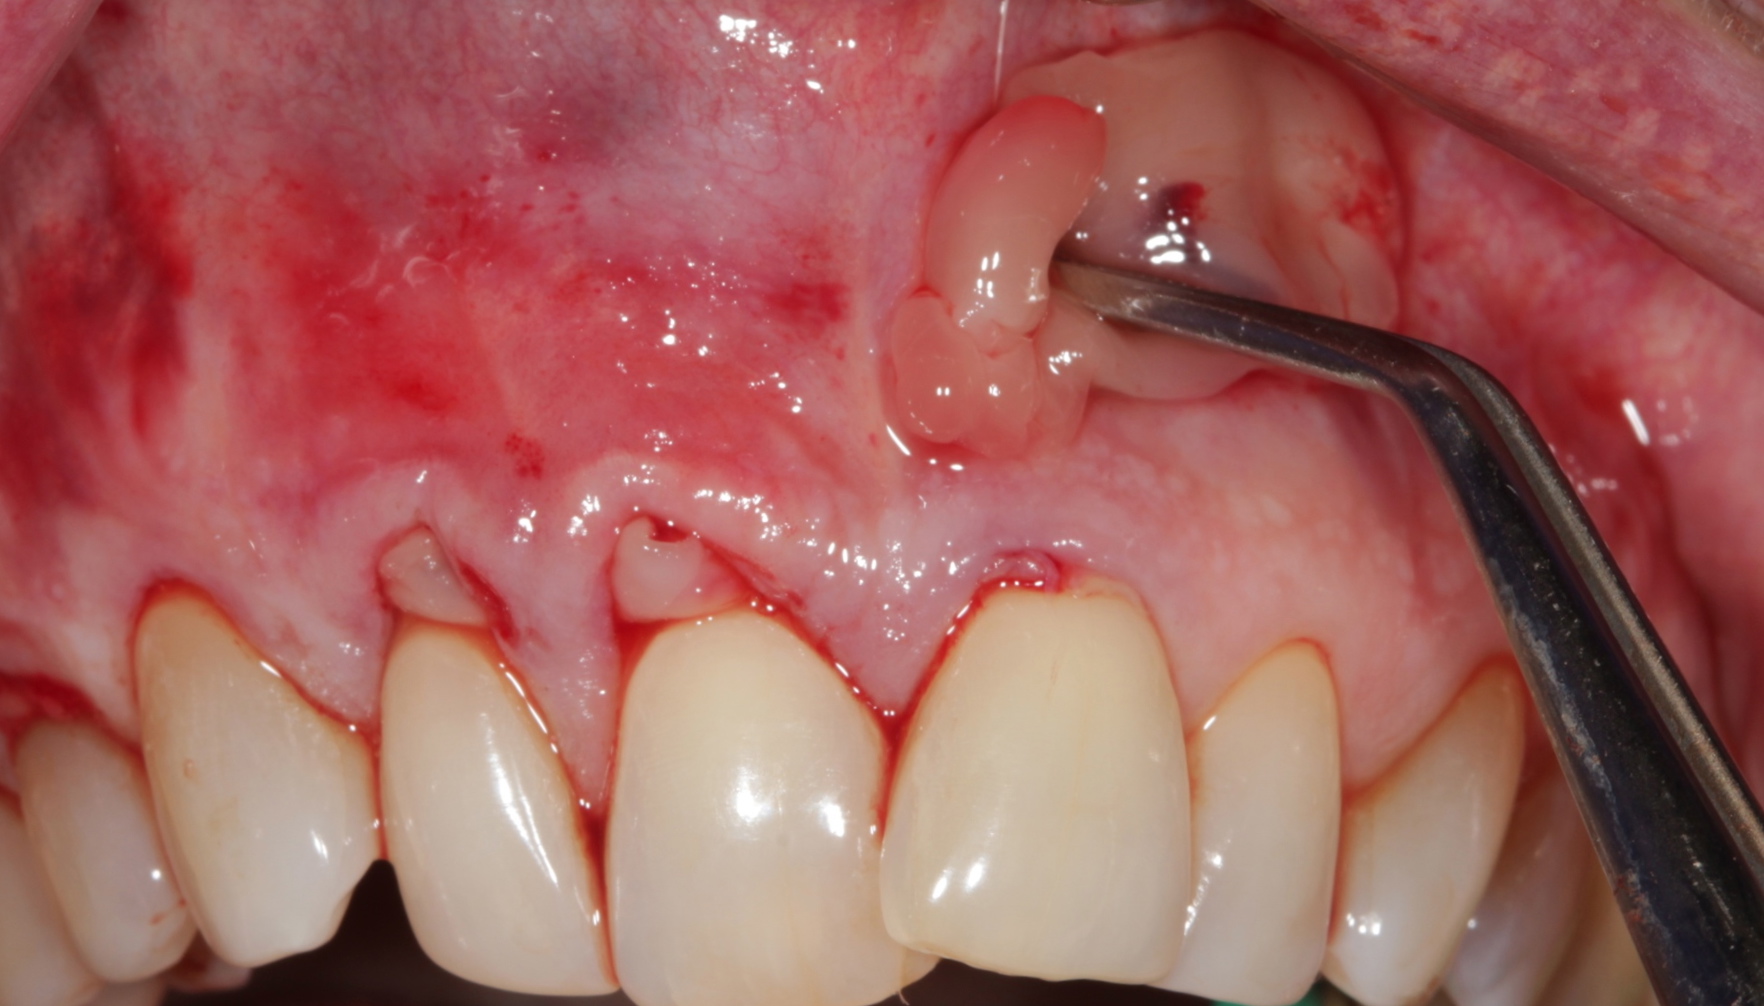

The surgical technique proposed is a simplification of the vestibular incision subperiosteal technique access31 and an improvement of the tunnel technique.32

Incision

The vertical mucosal incision will allow a horizontal (mesiodistal) and apicocoronal full-thickness flap instrumentation, resulting in a total relaxation and passive coronal displacement of the mucogingival papillary complex (Figure 5 and Figure 6).

Fig 5. Preoperative. Class 2 Miller trauma-induced recession and associated tooth malposition.

Figure 5

Fig 6. Incision and flap relaxation. A vestibular incision subperiosteal technique-access incision (horizontal mucosal incision) allows for a full-thickness horizontal dissection. A total flap relaxation enables the clinician to avoid uncontrolled flap pressure on the APRF membranes and allows complete and passive coronal positioning of the soft tissues.

Figure 6